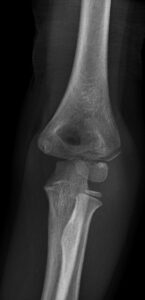

[toggle title=”Radiokapitellar Hat” state=”close”]

AP, Lateral ve Oblik grafilerde radius başının ortasından geçecek şekilde çekilen çizgi kapitulumun ortasından geçmelidir.

Bu hat üzerinde herhangi bir sapma radius başı çıkığını düşündürür. Bunun dışında lateral kondil kırıklarında da bu hat üzerinde bozulma görülebilir.

Radiokapitellar Hat Kapitulumun medialinde kalmış